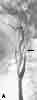

The initial CT scan of the brain showed a linear hyperdensity in the region of the left middle cerebral artery, which indicated thrombus formation (Figure 1). An area of cerebral edema was noted in the region with a small effacement from left to right. A cerebral angiogram performed 6 hours after the CT scan revealed a complete dissection of the left internal carotid artery (ICA) from the second cervical segment craniad (Figure 2). A follow-up CT brain scan 24 hours later demonstrated a large, left middle cerebral artery ischemic infarction with midline shifting and evidence of left uncal herniation (Figure 3).

Conventional intra-arterial angiography— long considered the “gold standard” of diagnosis—may no longer be necessary; the procedure poses the risk of cerebral complications. 8 Angiography may reveal a slowly tapering occlusion or an irregular longitudinal stenosis. A “string sign”— a segmental luminal constriction—is the most distinctive angiographic finding. 15 Another pathognomonic feature, the double-barrel lumen with mural flap, is found in only 4% of patients.